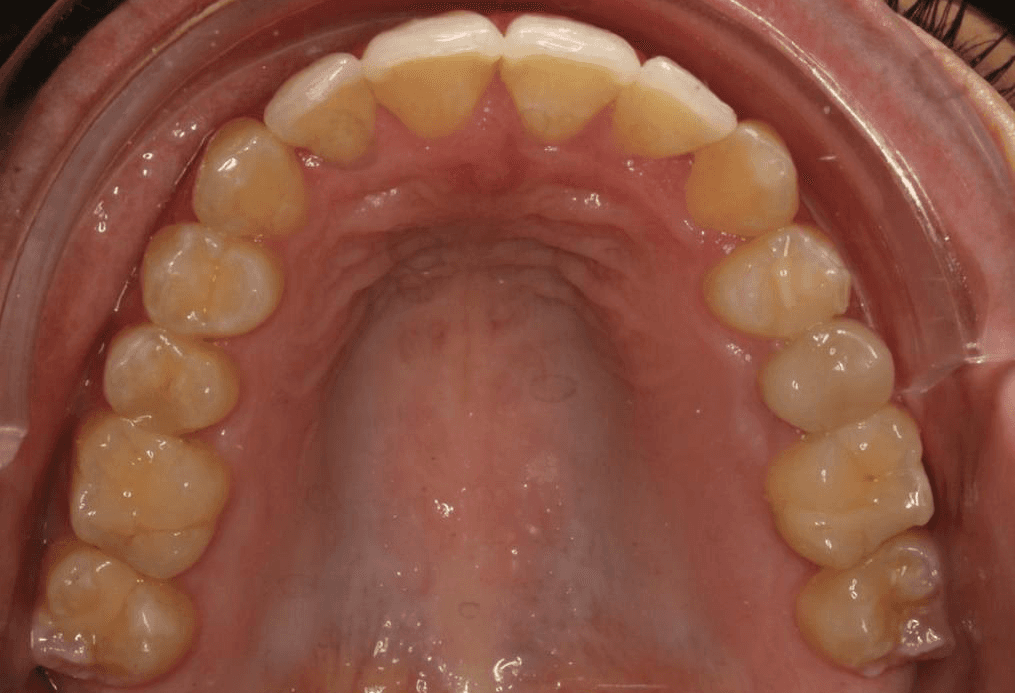

Initial treatment

INTRAORAL